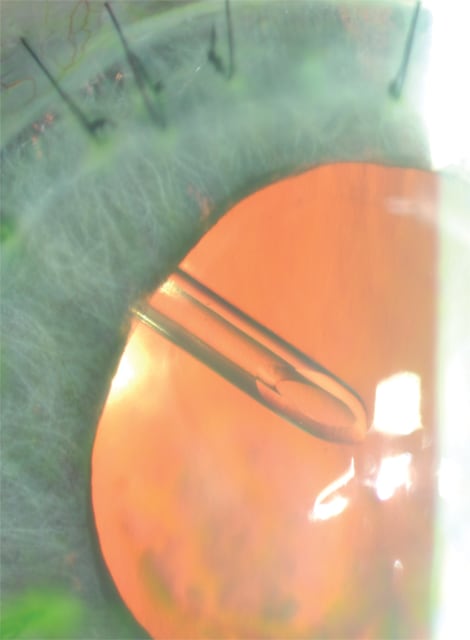

■ Intraocular entry. Insert the tube into the anterior chamber by creating a tract using a 23-gauge needle to enter the anterior chamber immediately posterior to the surgical limbus and parallel to the iris plane (Figure 3). GDI tubes are most commonly placed in the anterior chamber (Figure 4). However, in eyes at high risk for corneal decompensation, the tube may be placed in the ciliary sulcus to decrease the risk of corneal endothelial cell injury (Figure 5).

Figure 4. Adequate postoperative tube position in the mid-anterior chamber.

Figure 5. Adequate ciliary sulcus tube position in a patient that has undergone prior penetrating keratoplasty. Tube placement in the sulcus space minimizes risk of contact with the corneal endothelium.